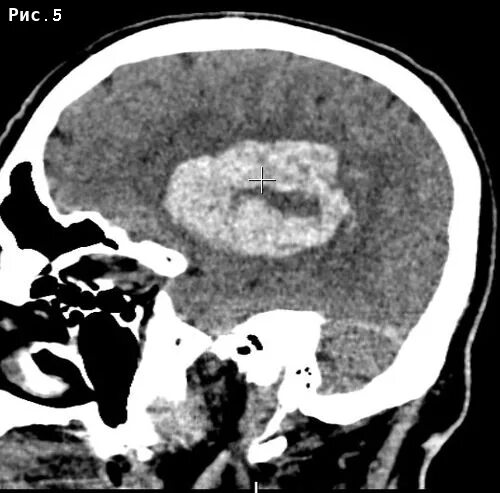

Объем гематомы на кт